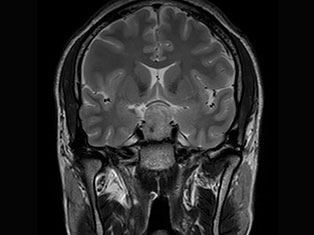

Brain Tumors

A brain tumor is a mass or growth of abnormal cells in your brain. Many different types of brain tumors exist. Some brain tumors are noncancerous (benign), and some brain tumors are cancerous (malignant).